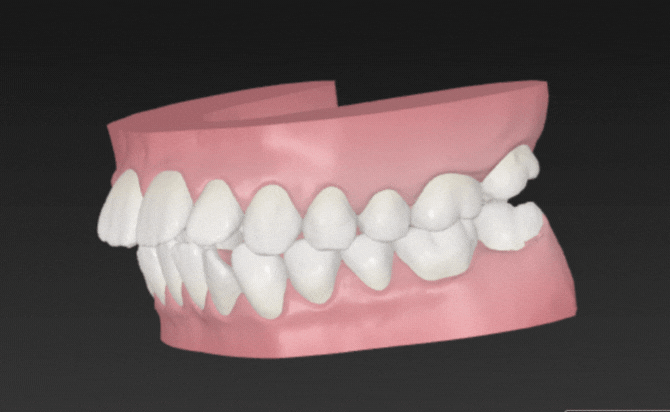

[4]マウスピース矯正症例|10代女性・出っ歯|佐賀市

口元の評価では、上顎前歯の前方位が認められ、軽度〜中等度の上下顎前突(出っ歯) が確認されました。

前歯の傾斜が強く、上唇の突出感にも影響していましたが、歯列全体のスペース不足は軽度であり、非抜歯での整列および前方位の改善が可能な状態 と判断しました。

咬合に大きな異常はなく、アライナーでのコントロールが適切におこなえる症例と判断しました。

IPR(歯と歯の間をわずかに削ってスペースを確保する処置)を適宜行い、前歯の傾斜を後方へコントロールする計画としました。

アタッチメントを併用し、前歯のトルクコントロール(傾きの調整)と全体的なアーチの整列を行い、口元の突出感を軽減することを主な治療目標 としています。